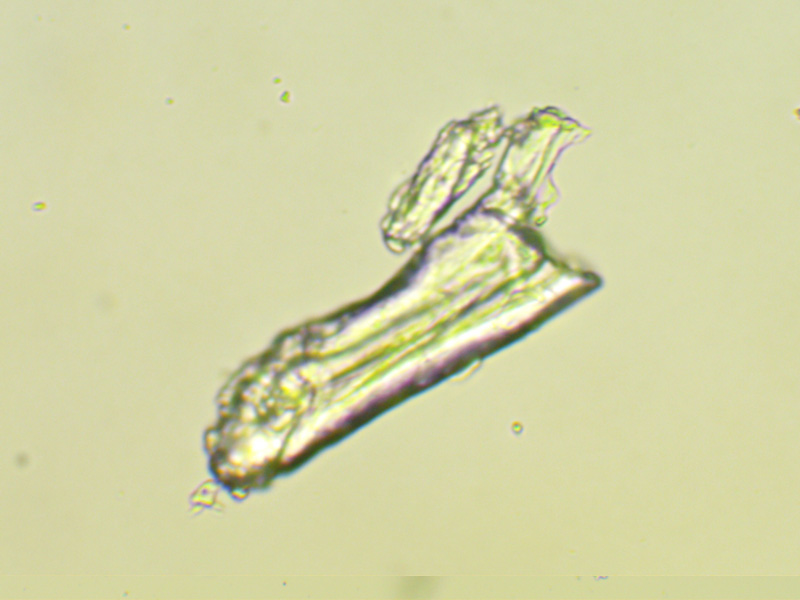

Zdjęcia mikroskopowe ujawniają niejednorodność substancji krystalicznych zawartych w tabletce Polfa Tarchomin, wskazując, że jest to mieszanina częściowo zmielonych kryształów. Występuje też pewna zawartość mikrokropelek cieczy.

Rys. 1 Zdjęcie mikroskopowe pokruszonej pastylki Polfa Tarchomin, mikroskop Evolution 100 firmy Delta Optical, obiektyw 10x

Obrazy mikroskopowe

Metoda spektroskopii cząstek pola torsyjnego umożliwia uzyskiwanie spektrów z obrazów mikroskopowych. Oznacza to, że z jednego kryształka lub ułomka kryształka widocznego pod mikroskopem możemy uzyskać informację jaki to jest związek nieorganiczy. W ten sposób zbadano dwa kryształki oznaczone na rysunku 1 jako A i B. Obraz fragmentu zakreślonego prostokątem A powiększono i wydrukowano drukarką laserową na folii poliestrowej, która bardzo dobrze przenosi fantomy cząstek pola torsyjnego. Wycięto obraz kryształka i osobno żółtej strefy, wskazującej na reakcję chemiczną kryształka z cieczą. Sygnały z wycinków przeniesiono akceleratorem cząstek pola torsyjnego na fiolki z wodą, które następnie zbadano spektroskopem cząstek pola torsyjnego. Uzyskane spektra  dla kryształka A przedstawione są na rys. 7.